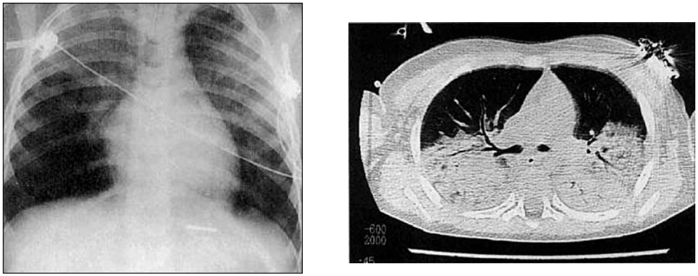

Paciente vítima de atropelamento, sexo masculino, 45 anos, altura 1,85 m, peso 80 Kg, após 3 dias na UTI, em IOT sob VM Modo Pressão Suporte com SatO2 = 88%, Pressão suporte (PS) = 25 cmH2O, FiO2 = 50%, Peep = 5 cmH2O, Volume corrente (VC) = 650 mL com hipoxemia de PaO2 = 57 mmHg, apresentou os seguintes exames de imagem, sendo descartada causa cardíaca.

(Arquivo pessoal; imagens usadas com autorização)